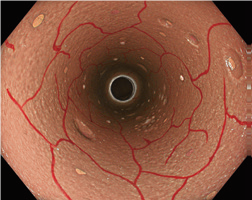

全焦点和高放大倍率,实现高清图像

EDOF技术

我们独特的扩展景深(EDOF)技术将近距离拍摄的图像与远距离拍摄的图像结合在一起,以生成具有更宽景深的图像,从而使您在整个图像区域内都具有更高的清晰度和更丰富的细节,从而确保连续进行出色的观察广泛关注。

全焦点

借助EDOF技术,CF-EZ1500DI/L在正常对焦模式下可以接近被摄物体3 mm,提供清晰,清晰的视图,从而可以减少日常使用中调整对焦的需要。(来源:成贯仪器)

白光 正常聚焦 NBI近焦

高倍率和双焦点

通过简单的内窥镜开关进入近焦点模式时,CF-EZ1500DL/I可提供高倍率*,从而可以更好地观察细节。高放大率和宽景深的结合,即使从切线方向,无论对象是否运动,都可以在整个视场中获得更清晰,更详细的成像。CF-EZ1500DL/I的先进光学器件与我们久经考验的NBI技术相结合,旨在帮助进行准确,高置信度的光学诊断。

*最大放大倍率分别为75倍(使用OEV262H)和90倍(使用OEV321UH)